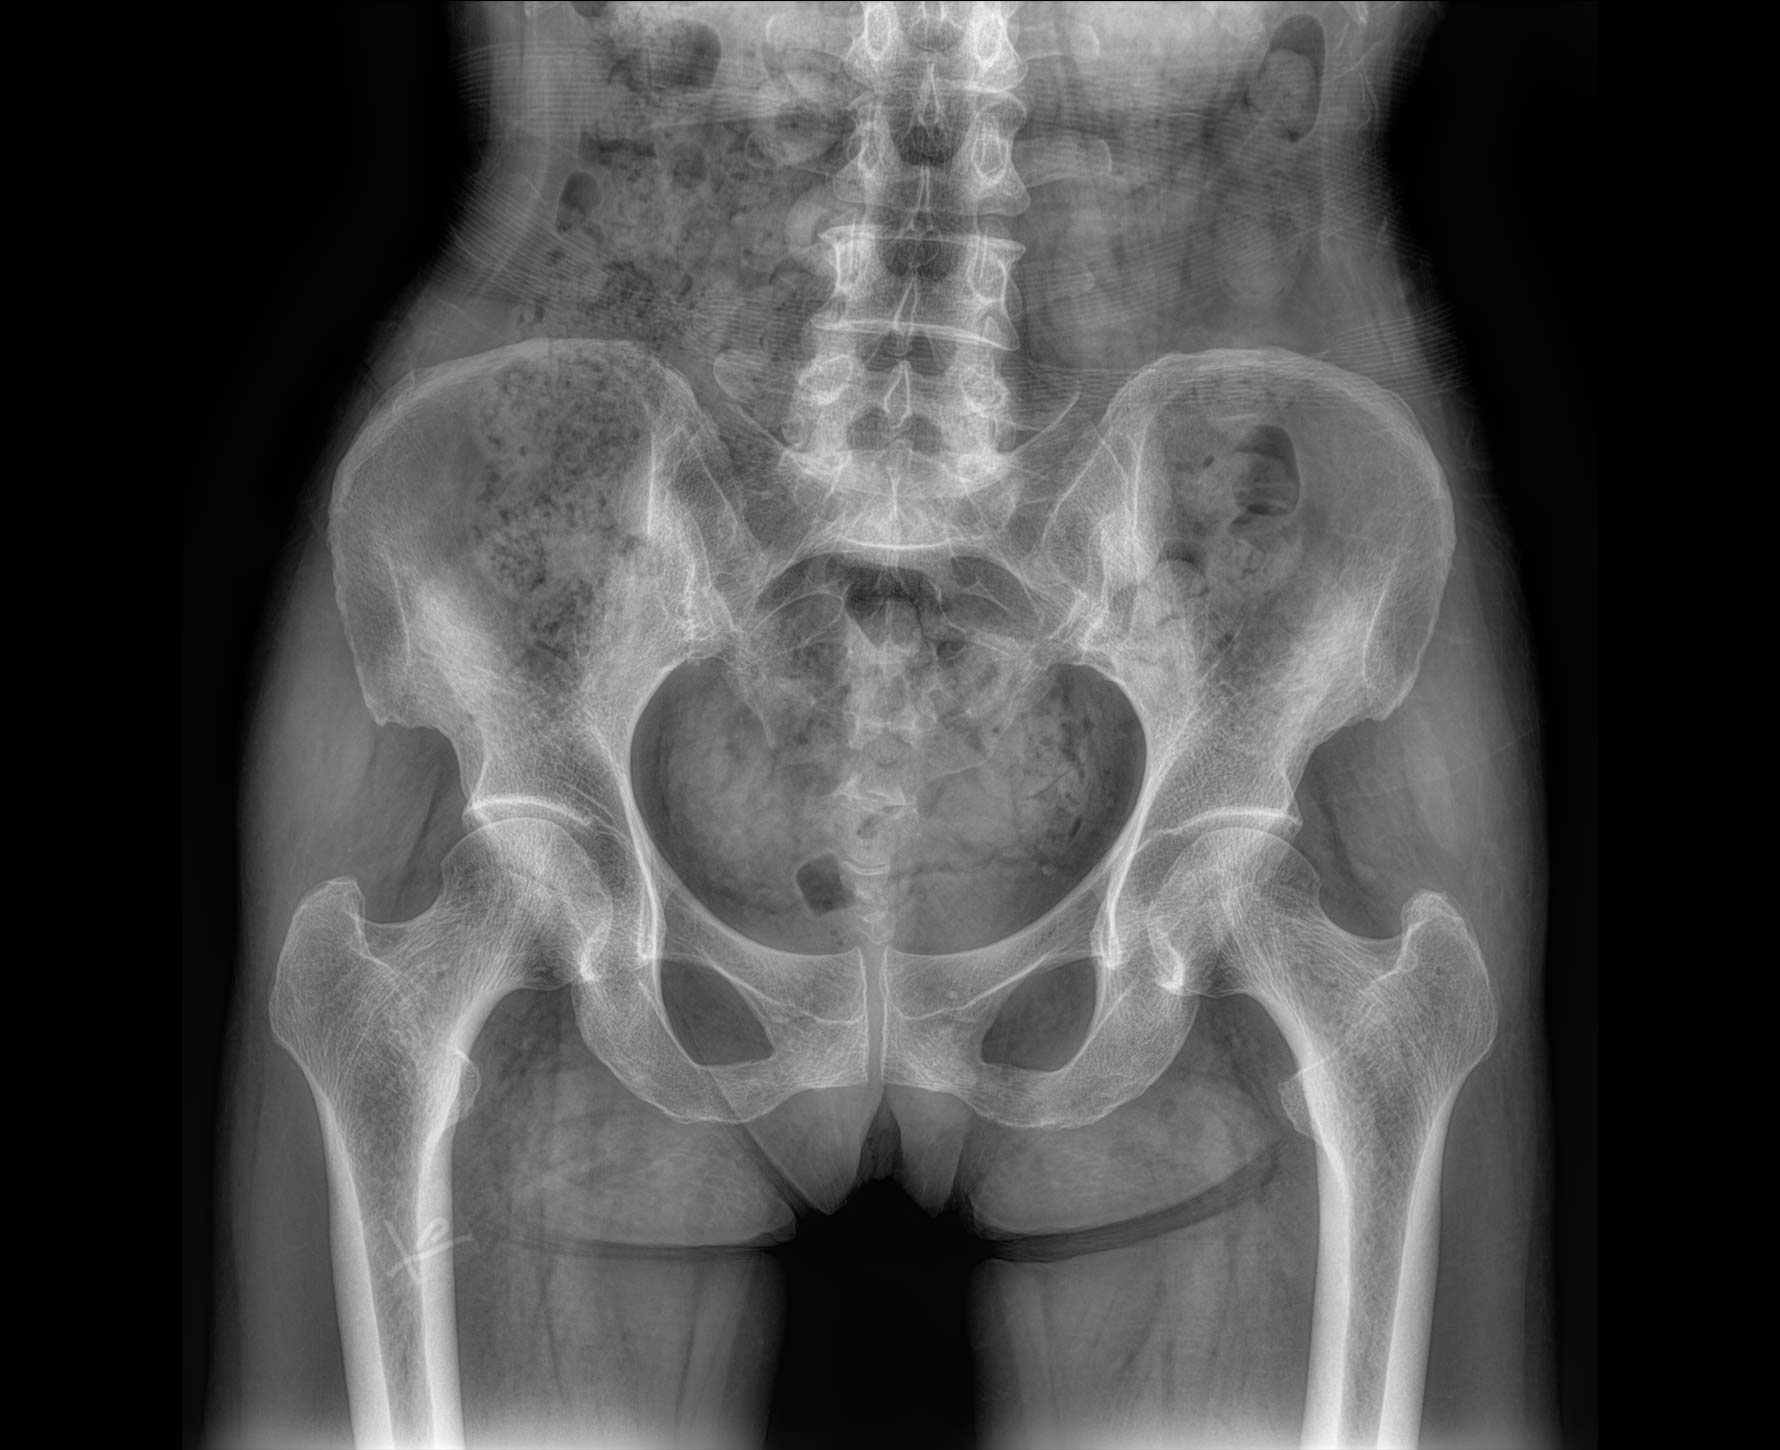

• 拍片

适用于全身各部位摄影

(常规摄影和特殊摄影)

临床图像